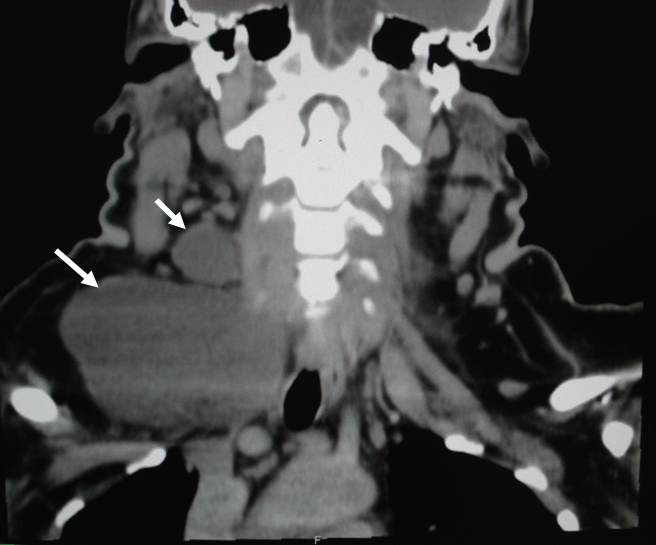

No changes in voice, dysphagia or pain at the lump were noticed. Only two years history of type II diabetes mellitus which was well controlled by oral hypoglycemic drugs was recorded. No history of head and neck irradiation or surgery was confirmed. Physical examination revealed an 8.0 x 6.0 cm, cystic mass at the right supraclavicular region. It was mobile with movement when swallowing. The thyroid gland was of normal size with no palpable nodules. Cervical lymph nodes were not palpable. Hematological and biochemical tests revealed no abnormalities. Computed tomography (CT) of the neck showed two non-calcified cystic masses measured 8.6 x 5.2 cm and 3.0 x 2.7 cm. Both were located at the right mid-jugular and right supraclavicular regions, respectively (Figure 1). Lower border of this cystic mass is seen in figure 2.

Figure 1: CT (saggital view) - Two cystic masses at right middle jugular area and downward to supraclavicular region (arrow).

Figure 2: CT (coronal view) - Lower border of mass at right supraclavicular region.